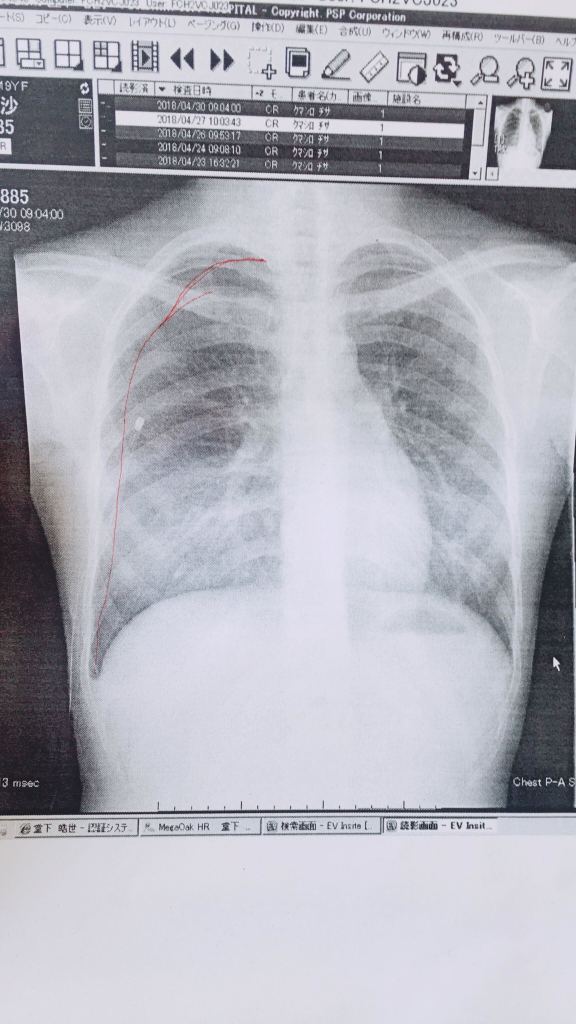

さあ、大学こそあちこち自分のお金であちこち行くぞーと思ってバイトを開始。アメリカ横断?ヨーロッパ周遊?ニュージーランドとかももいいな…なんて思っていたところ、肺に穴が開く病気(気胸)を発症。

しかも軽めならちょっと息苦しい、、で住むところ大きな穴が同時に2つ。救急車で搬送⇨緊急手術でチューブ刺される⇨終わったと思ったら「しばらく飛行機乗れない、ダイビングは一生禁止」との診断。

再手術をしてからは順調に回復以来、大きな再発はなく健康体です。

でも健康って当たり前にあるものじゃないんだなあという実感をした経験でした。